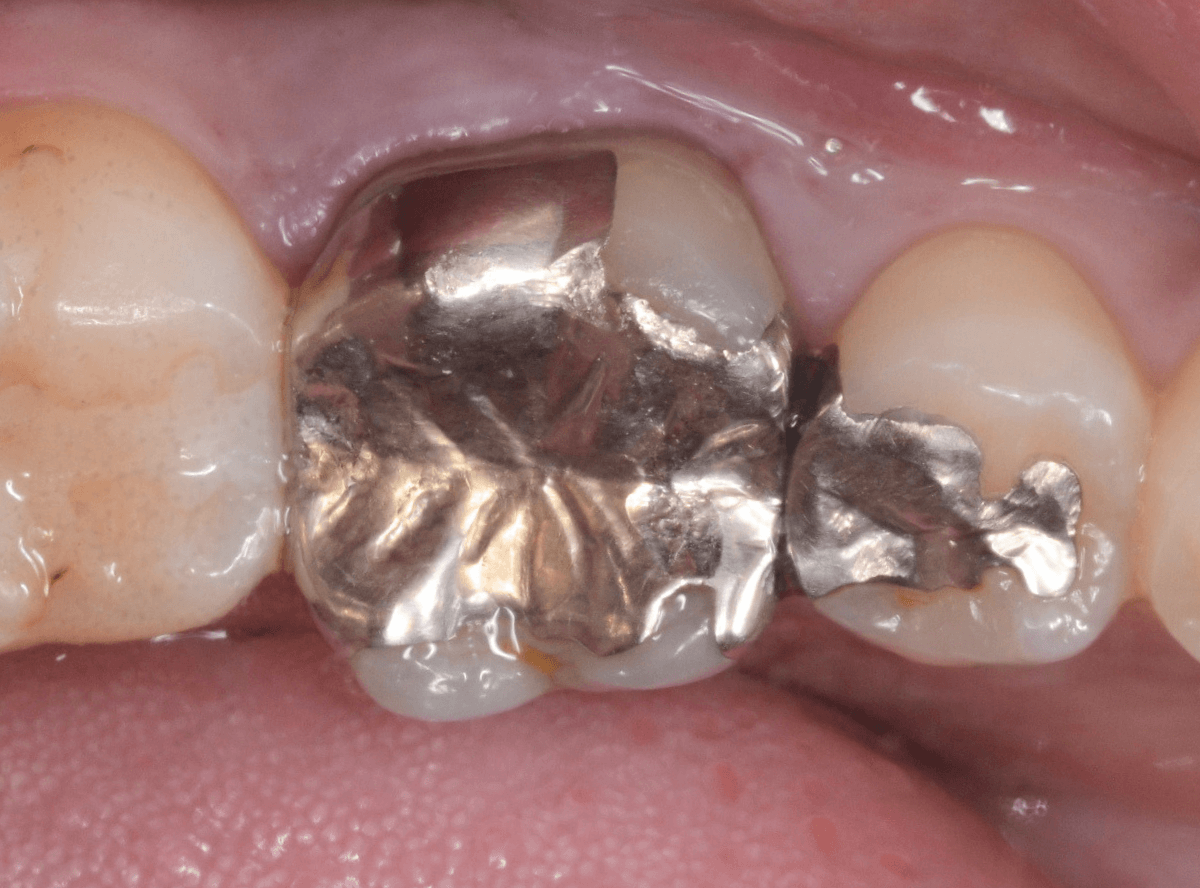

メタル・インレーとメタル・クラウンが入っていますね。

まずは、奥のメタル・クラウンを外します。

メタル・コアが入っていますが、こちらも慎重に外して、中を調べていきます。

レントゲン写真では問題なさそうでしたが、メタルコアを除去すると、中は真っ黒でした。

このように、コアの中で虫歯が進行している場合もありますので、さし歯をやり直す際は、出来る限りコアも外して調べるようにしています。